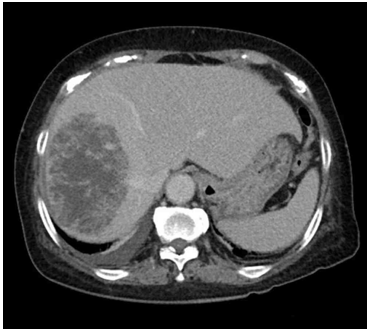

54세 남자가 1개월 전부터 오른쪽 윗배가 불편해서 병원에 왔다. 2년 전부터 수차례 고름담도염으로 항생제 치료를 받았다고 한다. 최근 3개월 동안 체중이 7 kg 줄었다. 혈압 110/60 mmHg, 맥박 80회/분, 호흡 14회/분, 체온 36.5°C이다. 배에 압통과 반발압통은 없다. 혈액검사 결과는 다음과 같다. 복부 컴퓨터단층촬영 사진에서 주변 조직 침범이나 원격 전이는 관찰되지 않는다. 치료는?

CT: Irregularly marginated mass with hyperattenuating rim and hypoattenuating center

• 자세한 평가를 위해 시행한 CT 영상에서 경계가 불규칙하고, 고음영의 경계저음영의 내부를 가진 거대한 종괴가 간에서 관찰되었다. 간 내 발생한 종괴의 경우 간세포암, 간내담관암과 같은 악성 종양, 또는 간혈관종, 간낭종과 같은 양성 종양을 고려해야 한다.

• 환자의 체중 감소와 CT 소견을 바탕으로 악성 종양 가능성이 강하게 의심되며, 혈액검사에서 AFP, ALT, AST 수치가 정상 범위에 있는 점으로 미루어 간세포암 가능성은 낮다. 영상 소견 및 혈액검사 결과를 종합할 때 간내 담관암으로 판단할 수 있다.